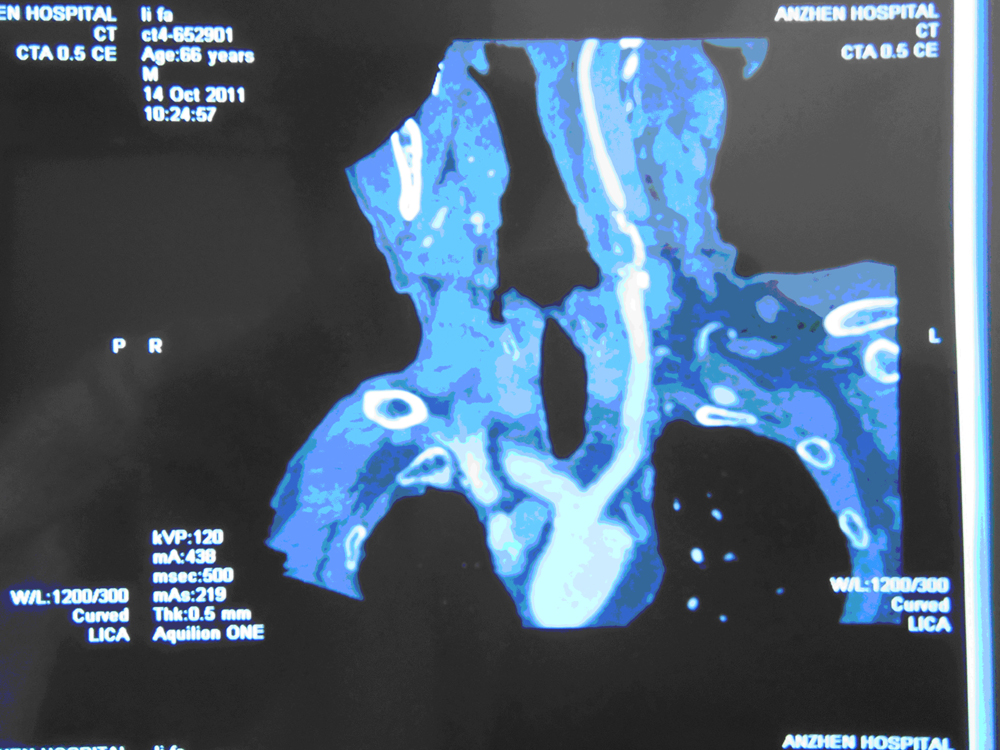

双侧颈内动脉重度狭窄右眼发作性黑曚

患者李某,男,66岁,主因“右眼发作性黑曚1月余”入安贞医院36病房脑卒中治疗中心。

颈动脉CTA:双侧颈内动脉近段管腔重度狭窄,不除外闭塞;

头部血管CT造影:左椎动脉远端发育纤细,管腔显影不良,不除外狭窄;头部灌注未见明显异常。

颈部血管超声:右侧颈总动脉分叉处至颈外动脉起始前壁混合回声斑块,分叉处中度狭窄;右颈内动脉起始前后壁强回声斑块,管腔闭塞;双椎动脉中度狭窄;左颈内动脉起始后壁混合回声斑块,重度狭窄;左椎动脉内径较对侧细。

DSA:  双侧颈内动脉重度狭窄     二、初步诊断

双侧颈内动脉重度狭窄

患者老年男性,主因“右眼发作性黑曚1月余。”入院,脑血管造影示双侧颈内动脉重度狭窄。2011年11月3日于安贞医院行左颈动脉内膜剥脱术,手术者张勤奕教授。术后患者恢复良好,顺利出院。